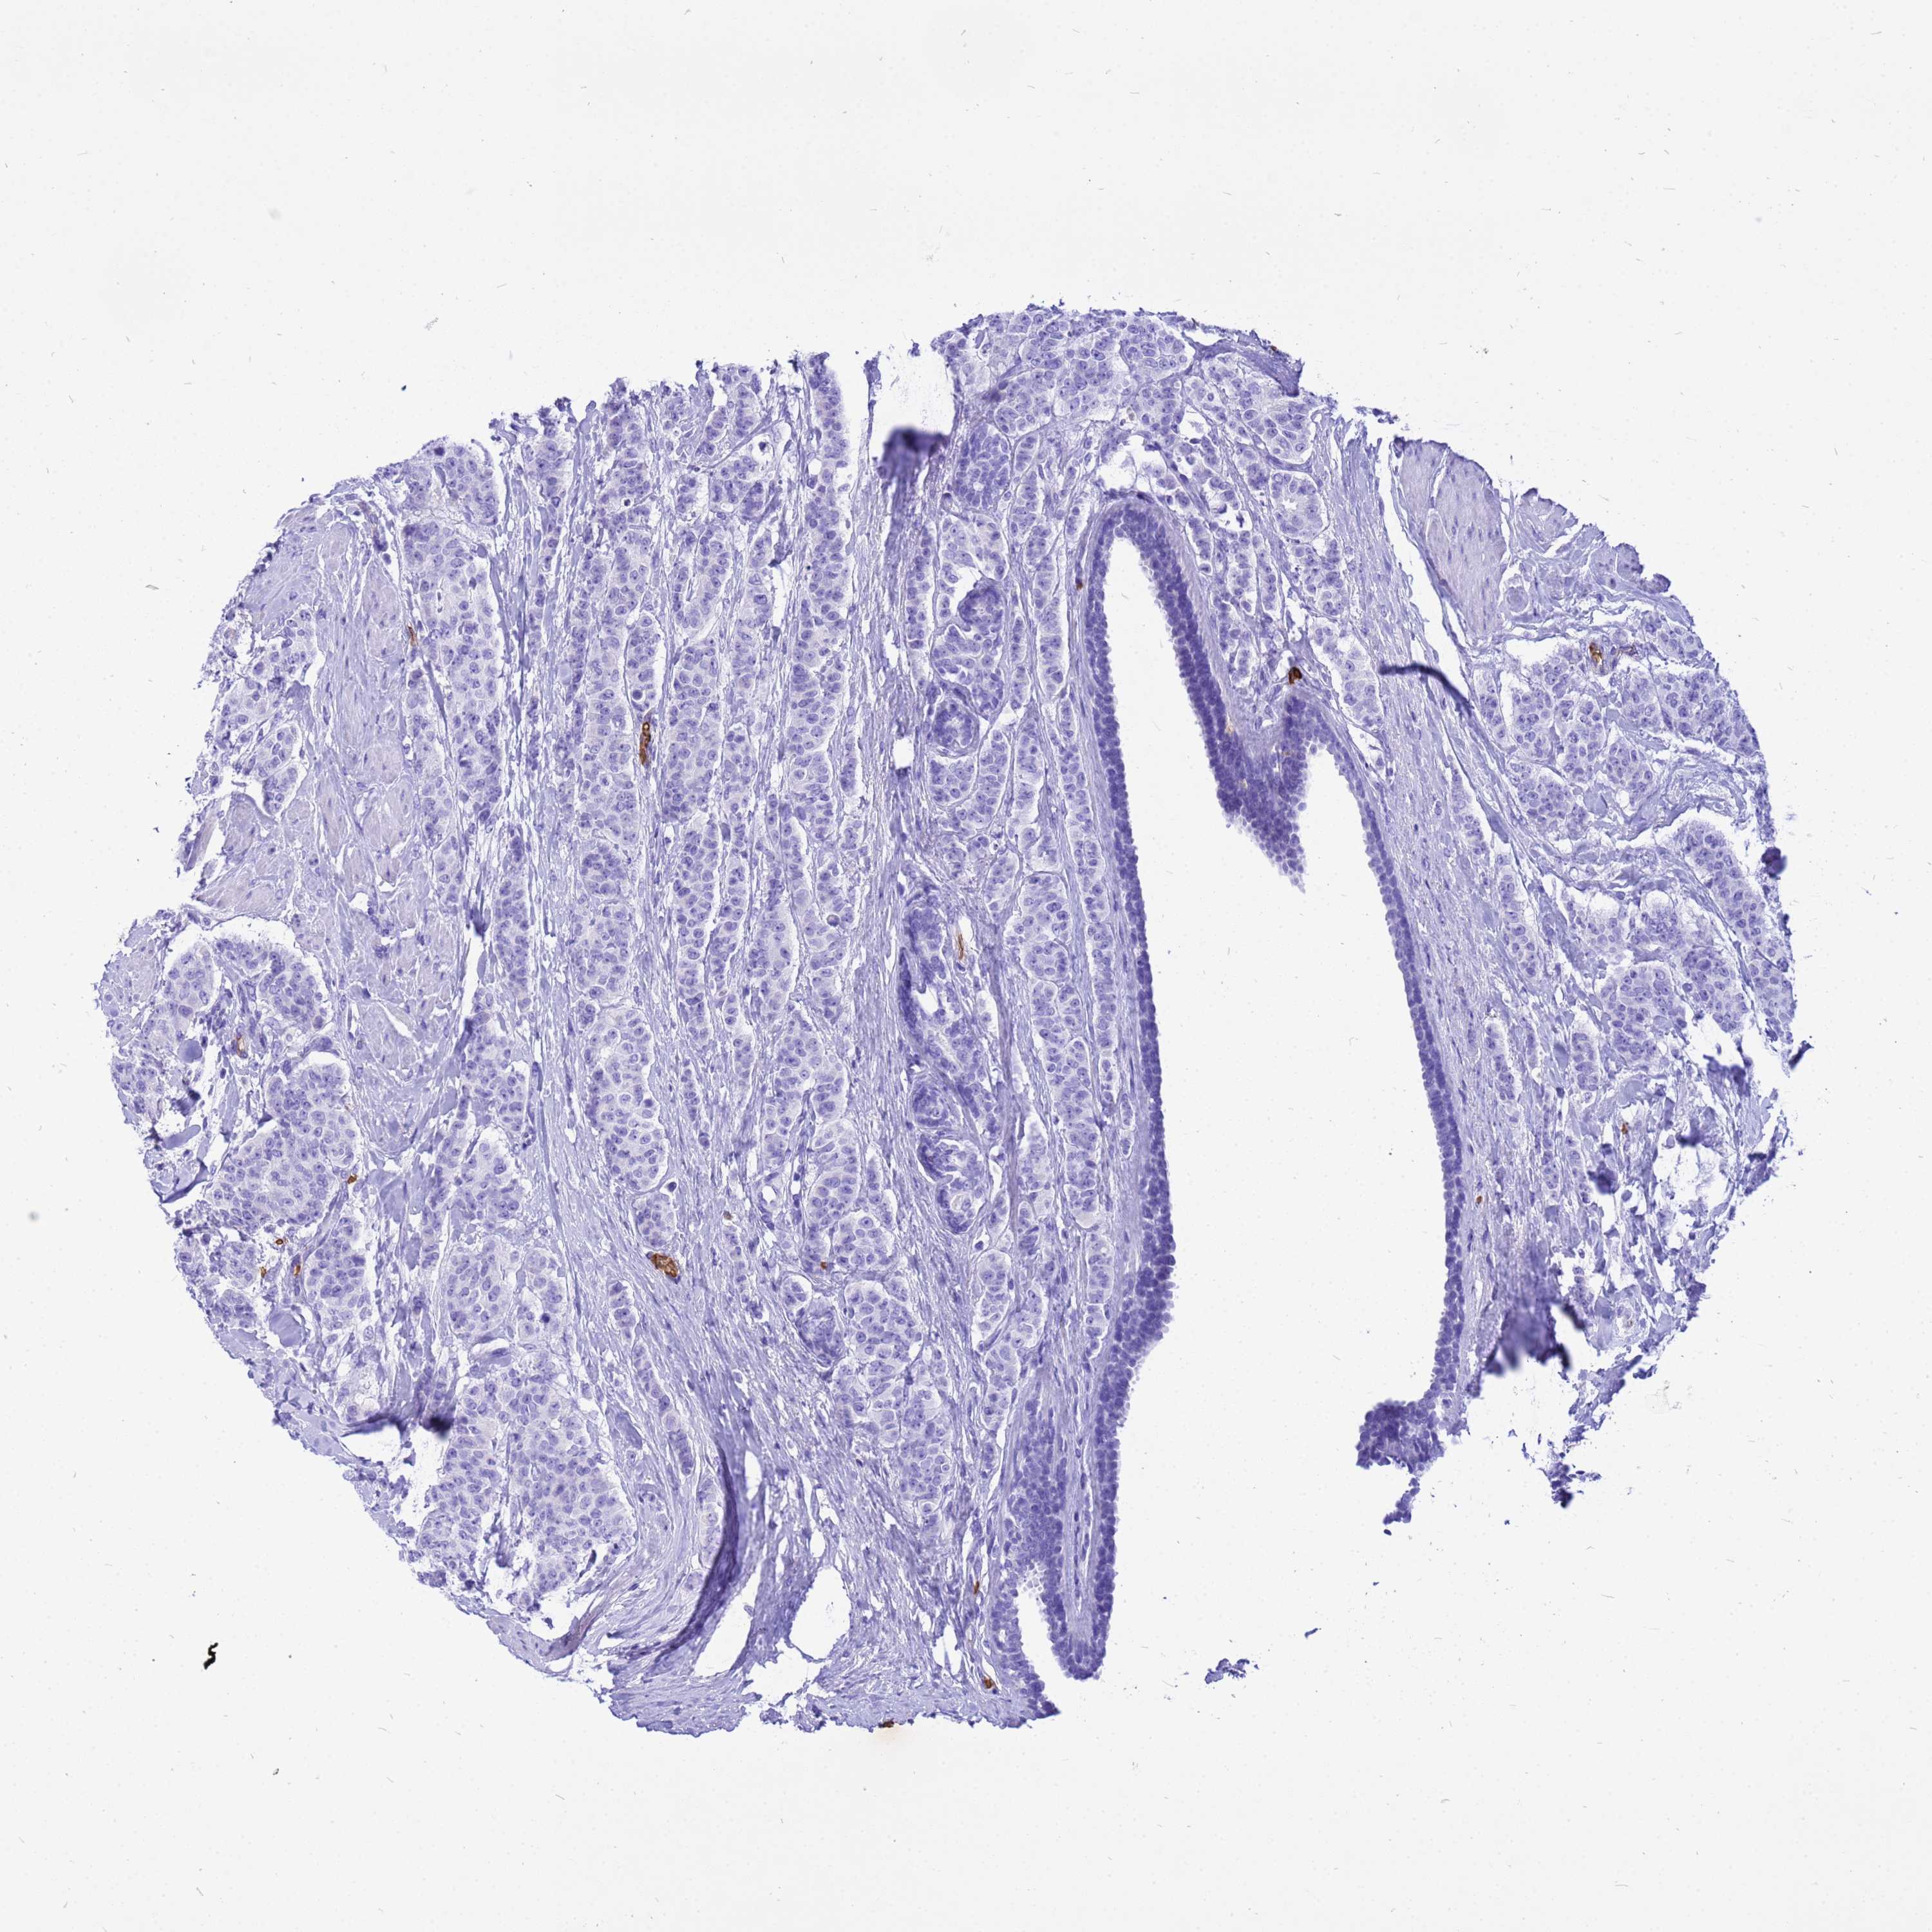

Breast cancer

Human cancer